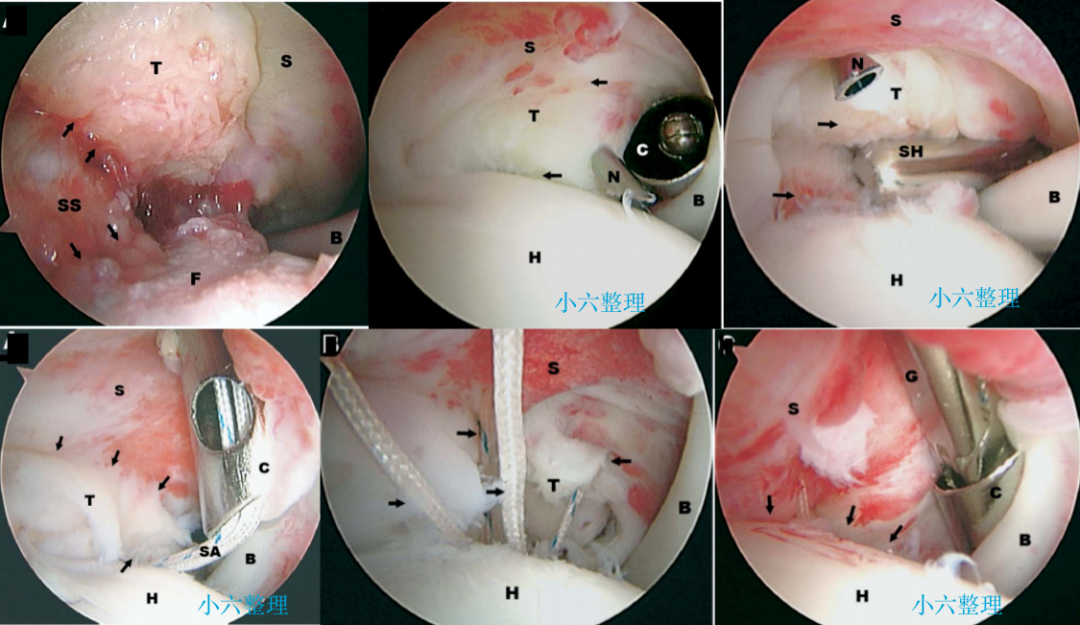

目前常用的外科技术

肱骨大结节骨折 ORIF,术前 X 线片显示肱骨大结节骨折情况;术中暴露肱

肱骨大结节骨折 ORIF,术前 X 线片显示肱骨大结节骨折情况;术中暴露肱